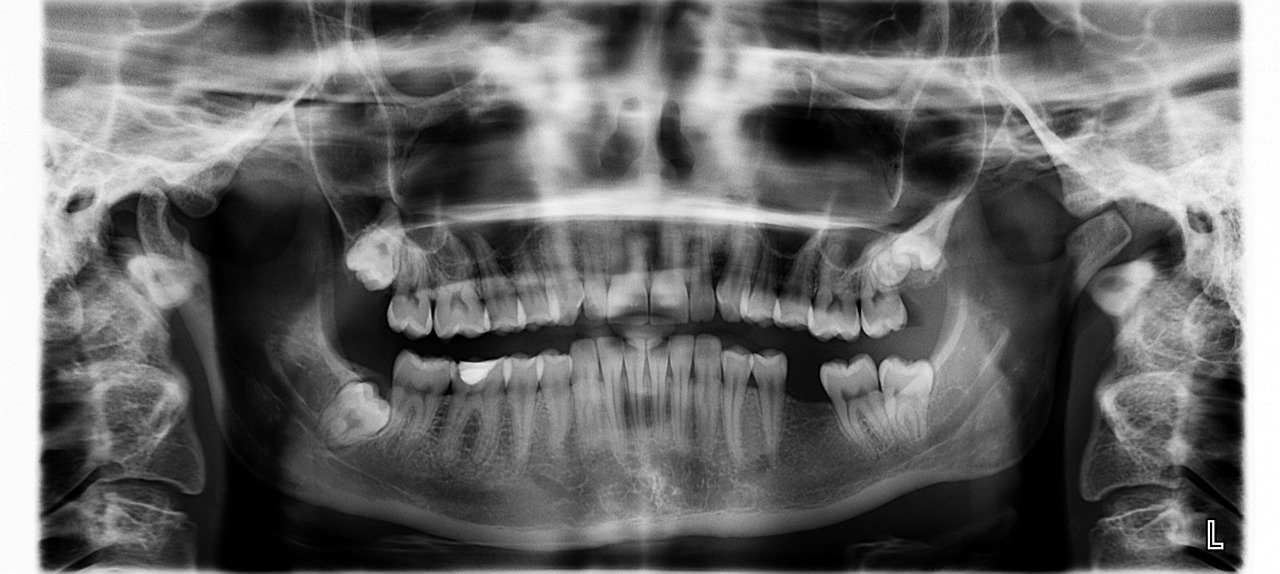

- 치과에 방문시 panorama 촬영 후 사랑니 위치와 매복상태를 확인한다.

- 사랑니와 하악 신경과의 관계를 파악하기 위하여 CT 촬영을 한다.

- 신경관에 근접한 사랑니는 사랑니전문치과나 대학병원으로 refer한다.